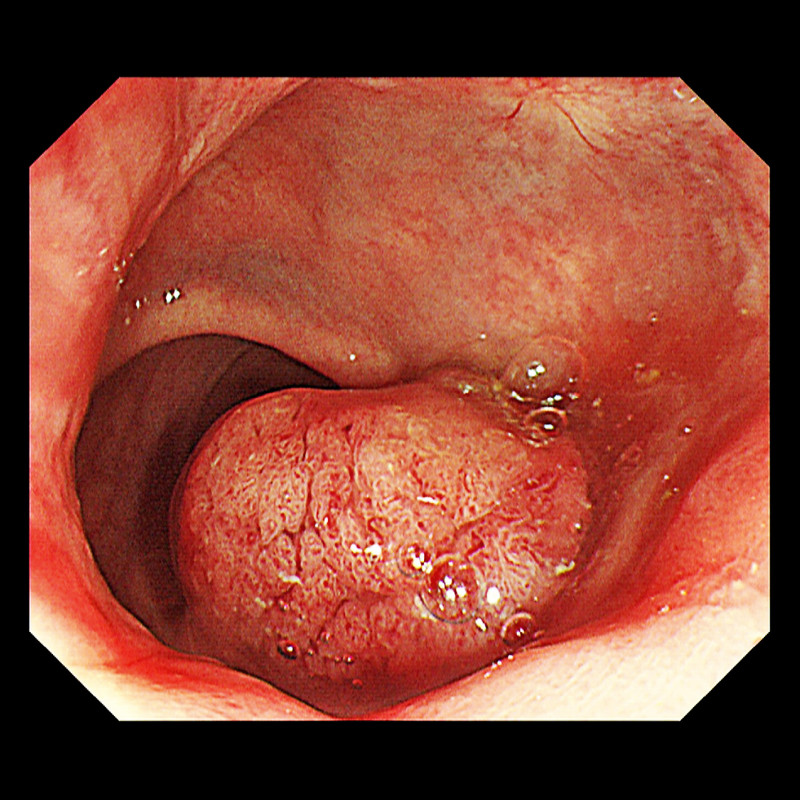

43歲趙先生左腹疼痛和腹脹1個多月,原以為是消化不良就醫,大腸鏡檢查卻發現直腸左側有1顆5公分腫瘤,為直腸癌第3期,驚訝雖然大便習慣改變,但無便秘、腹瀉,也無血便和家族病史,醫師呼籲要注意大腸癌年輕化的趨勢。高雄阮綜合醫院大腸直腸外科醫師蔡達基指出,大腸癌因為腫瘤的位置、大小和生長方式的不同,症狀會